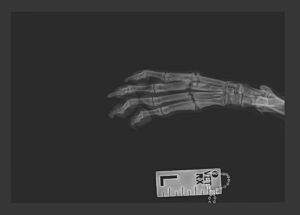

When she was home a little swelling was discovered on top of her paw. It didn’t hurt her and she didn’t limp but she was taken to the vet for an x-ray to be sure. It turned out her toes had been broken on that paw, probably a couple of months earlier. The X-ray showed it had healed beautifully, in a normal position, without further problems.